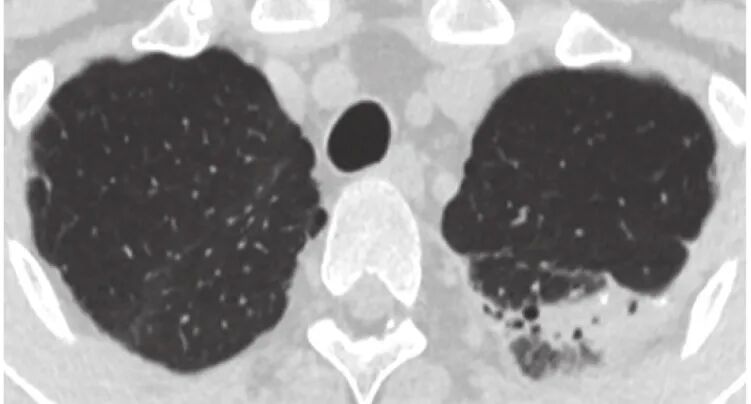

患者3,男,82岁,吸烟30包年,咳嗽、咳痰、喘憋30余年,诊断“慢阻肺”,长期使用ICS+LABA+LAMA。14年前曾查血清IgE 2407 IU/mL,5年前外周血嗜酸性粒细胞百分比升高(10.6%)。19个月前症状加重,胸部HRCT示双肺新增多发斑片影(图2),诊断为ABPA,予泼尼松联合伊曲康唑治疗,半年后血清IgE 降至550.5 IU/mL,复查胸部HRCT示双肺斑片影吸收,仍有反复喘憋加重,1年前因“急性心肌梗塞”死亡。

图2 患者3的HRCT检查像

a. 2019年7月5日,示双肺新发斑片影,其内可见支扩;b. 2019年7月30日,示双肺斑片影吸收,气道壁增厚。